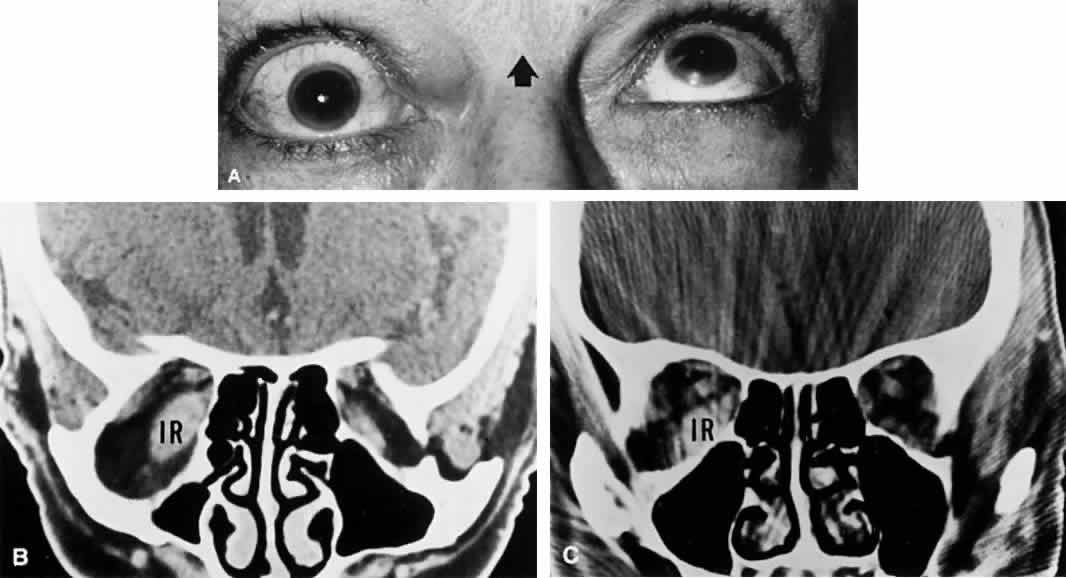

Oculomotor nerve palsies with orbital lesions are usually accompanied by abducens weakness and proptosis. In the absence of proptosis, anterior cavernous sinus lesions may not be distinguishable from those involving the superior orbital fissure or orbital apex. Nonspecific inflammations of orbital tissues (orbital pseudotumor) may produce palsies of extraocular muscles in variable combinations, but other manifestations (e.g., pain, chemosis, ocular inflammation, proptosis) are usually present. Orbital trauma, unless overlooked or forgotten, usually presents no difficulty in diagnosis. Forced duction testing and orbital ultrasonography and/or enhanced CT imaging are indicated.